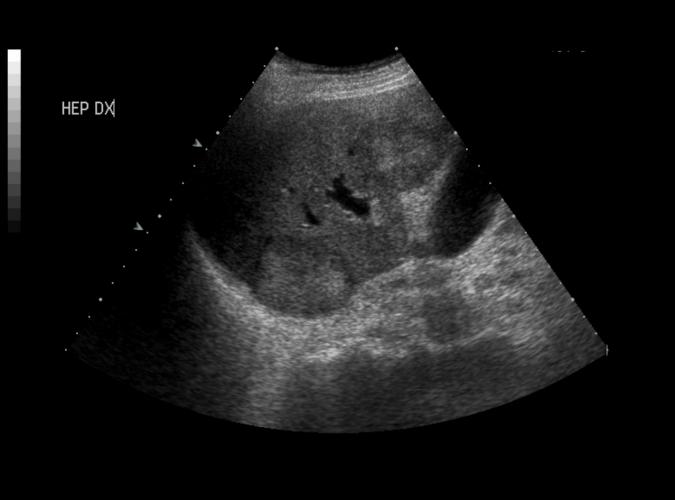

Fokala levermetastaser, känd coloncancer